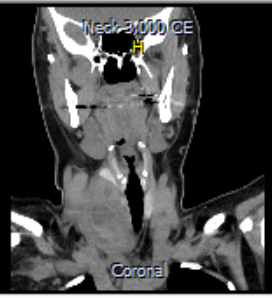

Se trata de una paciente de sexo femenino de 46 años con presencia de masa en hemicuello derecho asociada a disfagia mixta, emesis de contenido alimentario, odinofagia y pérdida de peso desde hace 1 año. Se realizaron estudios bioquímicos con hallazgo de hipercalcemia severa (17.2 mg/dl), PHT elevada y fósforo sérico normal. Se planteó diagnóstico de hiperparatiroidismo primario, solicitándose TC de cuello con hallazgo de masa de densidad heterogénea en relación al lóbulo tiroideo derecho asociada a adenopatías en el nivel VI, IIA bilaterales y IB a derecha (Figs. 1 y 2).